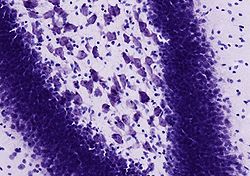

Nissl-Färbung

Die Nissl-Färbung, benannt nach Franz Nissl, ist eine histologische Färbetechnik, die insbesondere zur Darstellung von Nervengewebe verwendet wird. Dazu werden histologische Schnitte mit einem Farbstoff wie Kresylviolett, Toluidinblau oder Thionin versetzt. Diese Farbstoffe binden sich an basophile Verbindungen wie RNA und DNA und färben daher die Zellkerne und Ribosomen blau oder violett.[1][2]

Da im Nervengewebe die Ribosomen im Nervenzellkörper konzentrierter als in dessen Fortsätzen (Axon, Dendrit) vorliegen, werden nur die Zellkörper angefärbt. In diesen treten bei der Färbung die so genannten „Nissl-Schollen“ auf, welche dem rauen Endoplasmatischen Retikulum, an das viele Ribosomen angelagert sind, entsprechen.